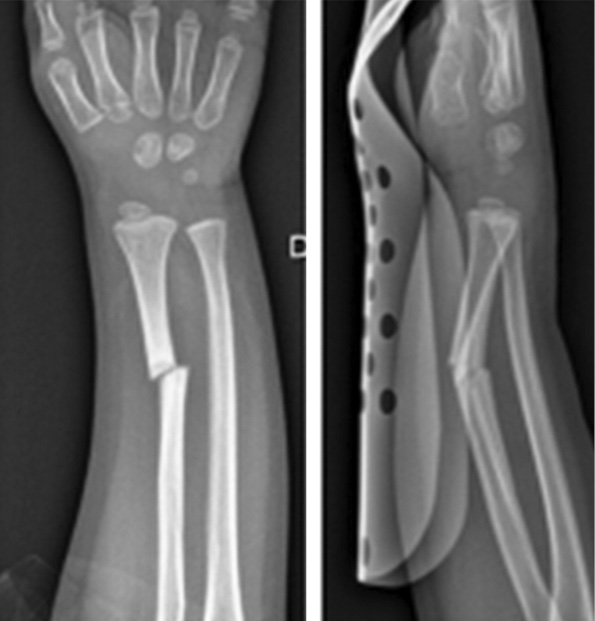

В декабре 2014 г. в отделение неотложной помощи поступил 4-летний мальчик после травмы правого предплечья с деформацией, болью и потерей функций, но без раны и без нейроваскулярной недостаточности. Установлен диагноз: «дистальный диафизарный перелом правой лучевой кости». Сломанная конечность была иммобилизована гипсовой повязкой. В январе 2015 г. появились признаки консолидации и гипс сняли. Через месяц после новой незначительной травмы пациент снова поступил в отделение неотложной помощи с диагнозом повторного перелома, но в этом случае у него был выявлен перелом со смещением дистальной трети правой лучевой кости (рис. 1).

Рис. 1. Повторный перелом через 3 мес.

При хирургическом лечении были использованы спицы Киршнера, но во время операции произошло осложнение в виде ятрогенного продольного перелома, который был синтезирован проволочным серкляжем. Примерно через 3 мес. после операции, хотя на рентгенограмме были незначительные признаки консолидации кости, металл был удален и предплечье было иммобилизовано новой повязкой (рис. 2).

Рис. 2. На рентгенограмме незначительные признаки консолидации кости, но металл был удален и предплечье иммобилизовано новой гипсовой повязкой